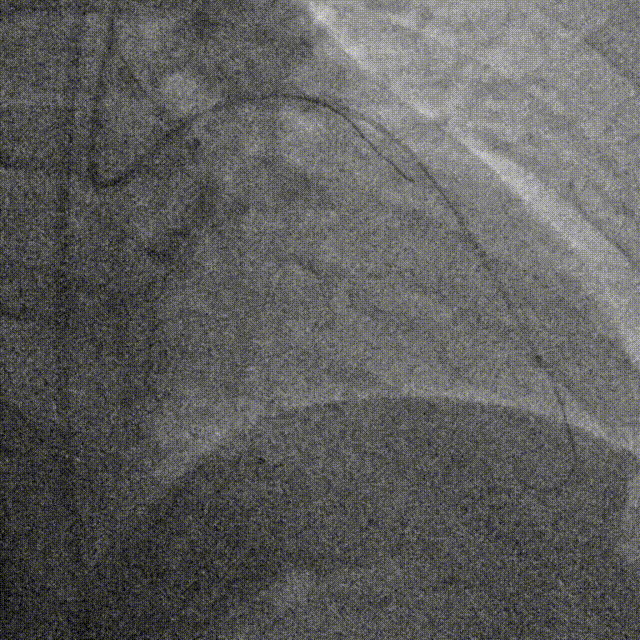

D1释放DCB,LAD植入支架后D1血流影响,工作导丝找回后使用球囊扩张并kissing。

造影发现LAD远端病变仍较重,释放DCB。

复查造影并行ivus检查 支架贴壁良好 无累及夹层。

RCA中段扩张后出现夹层,植入DES。